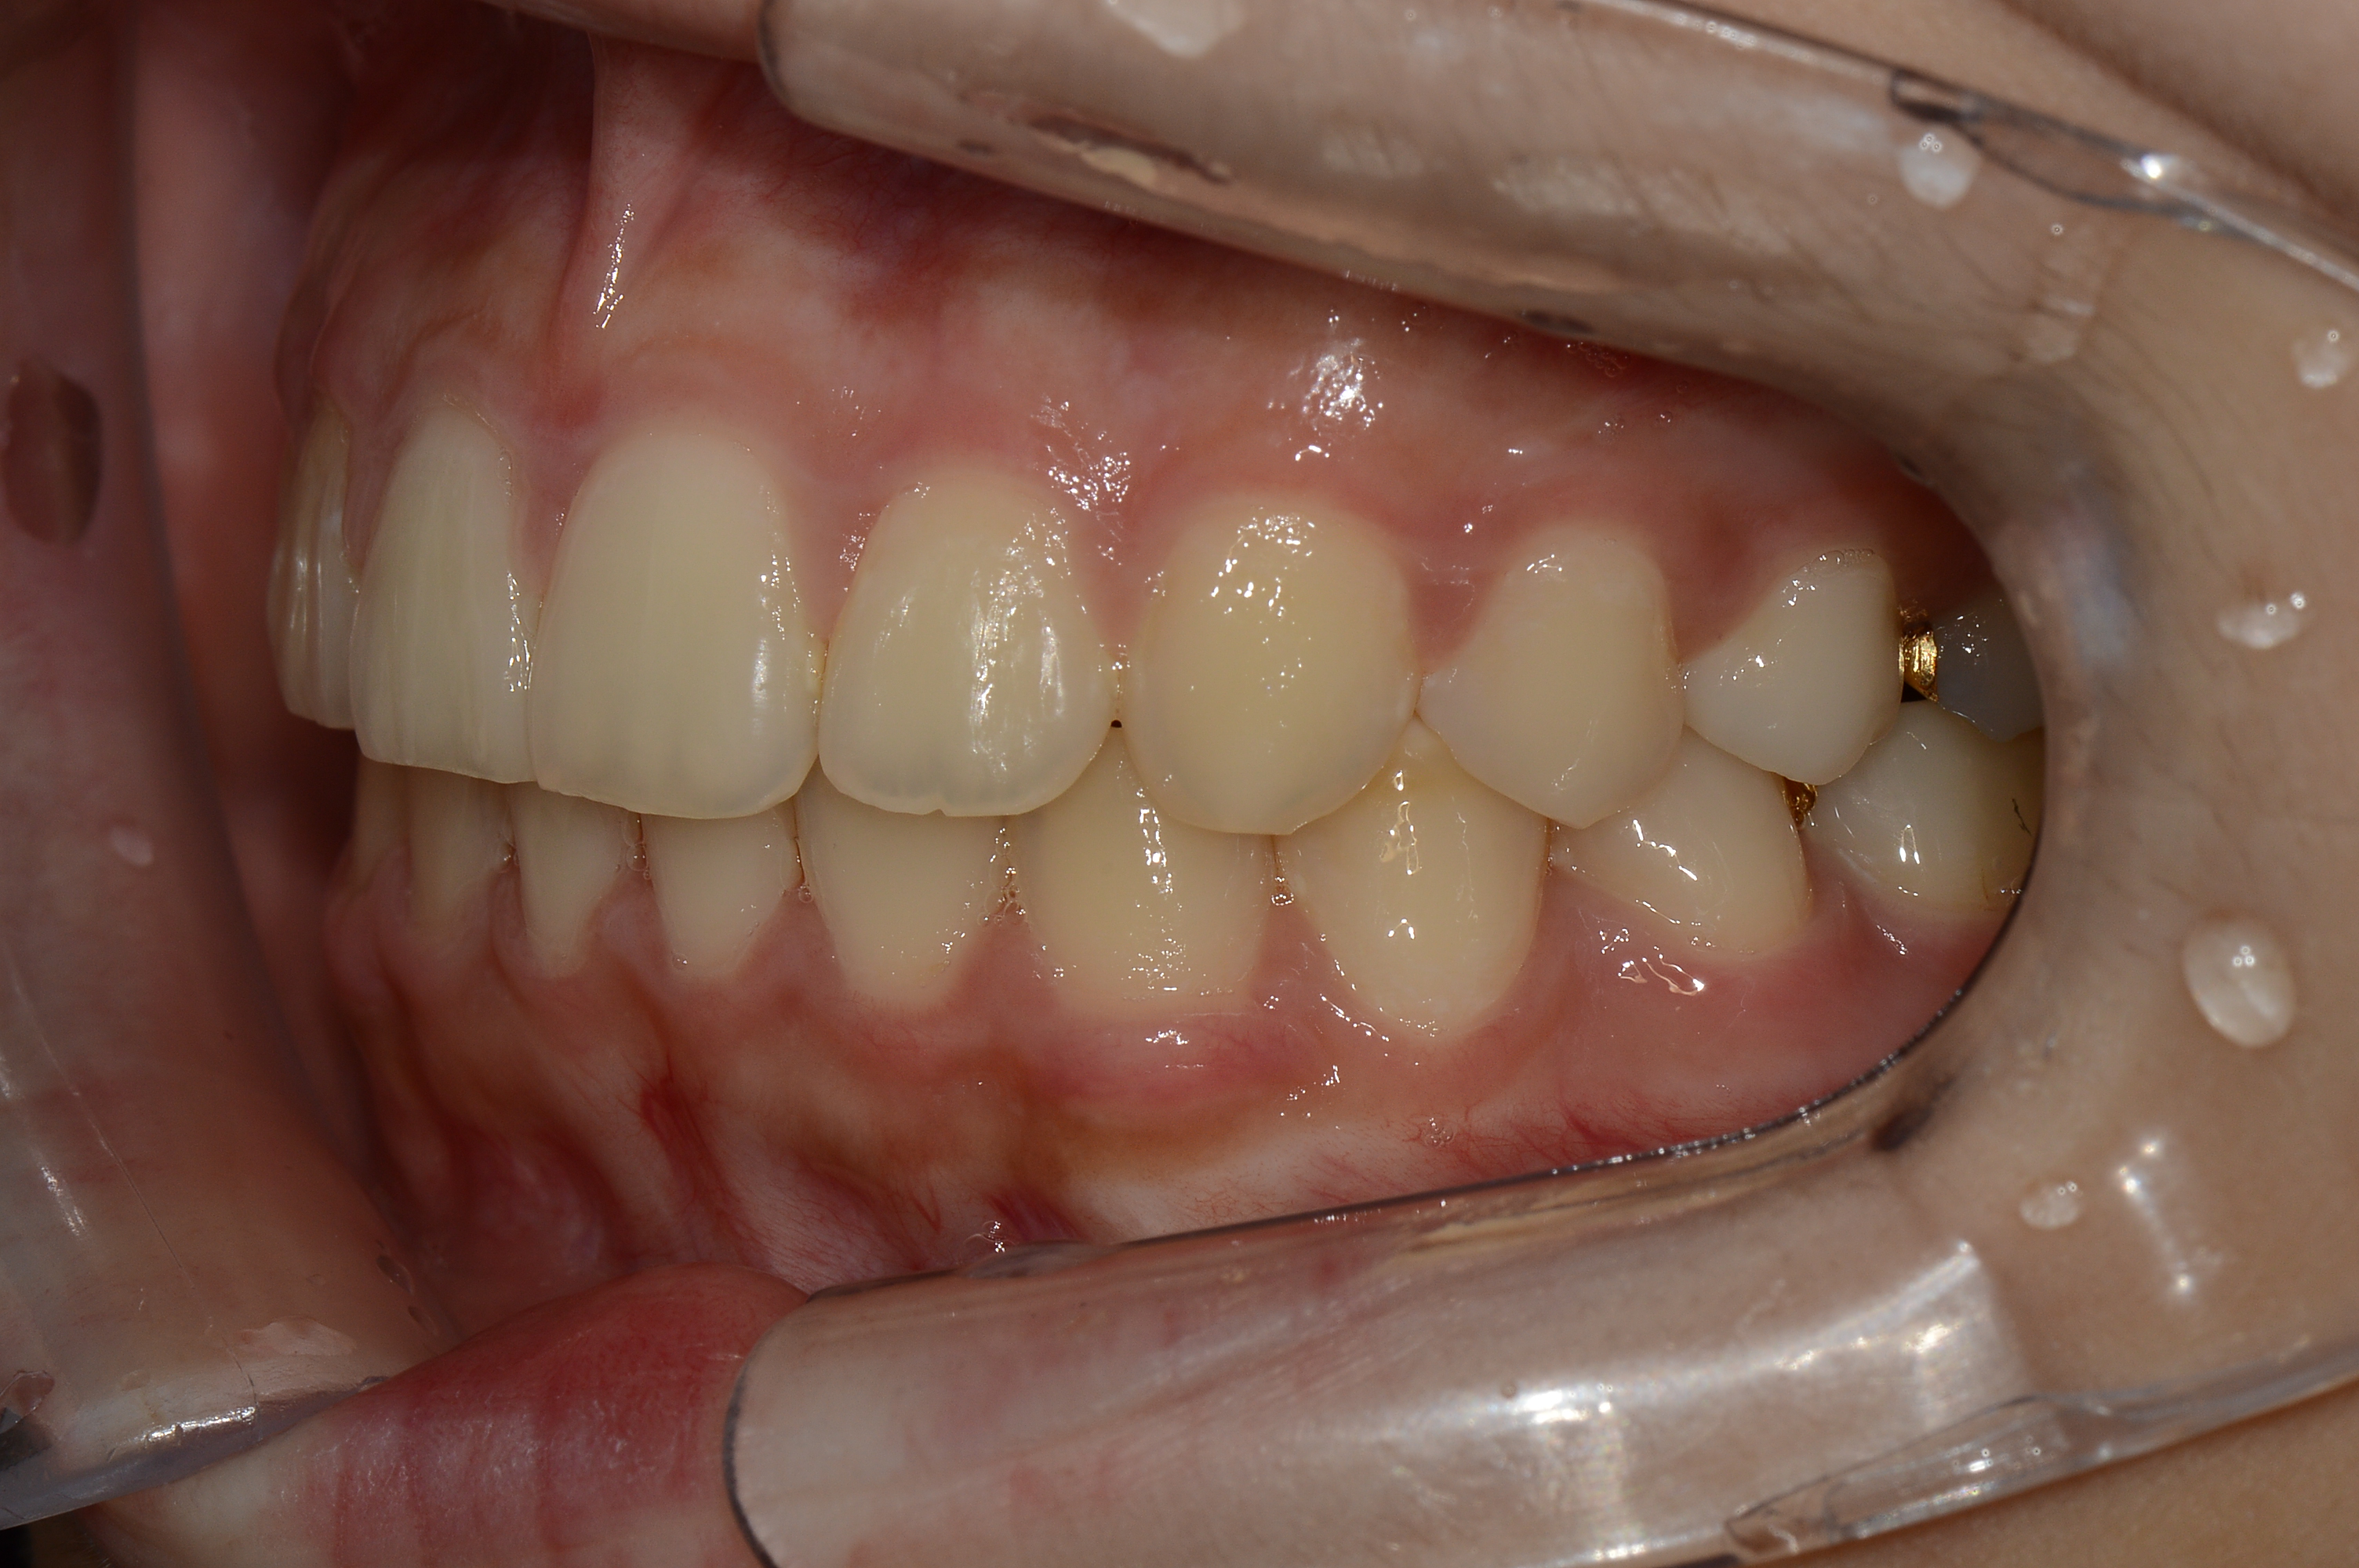

치료 전 사진입니다.